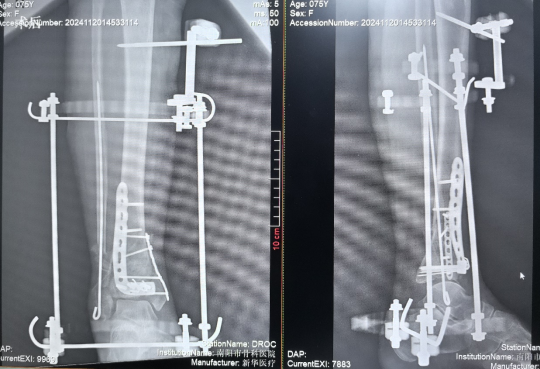

CO接骨機器人牽引下撬撥復(fù)位CO外架結(jié)合內(nèi)固定治療Pilon骨折

患者,女,75歲,主訴:踝部疼痛、腫脹,活動受限5天余。查體:右踝部畸形、腫脹明顯,局部按壓可觸及異?;顒蛹肮遣粮校钻P(guān)節(jié)活動明顯受限,足背動脈搏動可,足趾末梢血運及感覺尚可。診斷為右Pilon骨折見(Ruedi-Allgower III型)。

2.手術(shù)操作過程

1.CO外固定半環(huán)連接跟骨穿針并通過CO接骨機器人配套的連接桿與CO接骨器人中間機械臂相連,調(diào)整機械臂,進(jìn)行骨折端初步復(fù)位,C臂確認(rèn)復(fù)位滿意,關(guān)節(jié)間隙拉開。

2.CO接骨機器人持續(xù)牽引維持復(fù)位,選擇前外側(cè)切口對前外側(cè)骨塊進(jìn)行撬撥復(fù)位,并用克氏針進(jìn)行臨時固定。C臂透視復(fù)位滿意,放置兩塊鋼板進(jìn)行固定。

3.在脛骨近端穿入一根克氏針,連接CO外固定架進(jìn)行固定,并外踝處穿入一根克氏針進(jìn)行固定。C臂透視位置滿意,縫合結(jié)束手術(shù)。